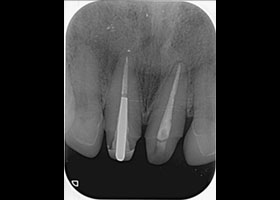

1. 術前口內正面照、局部X光片。